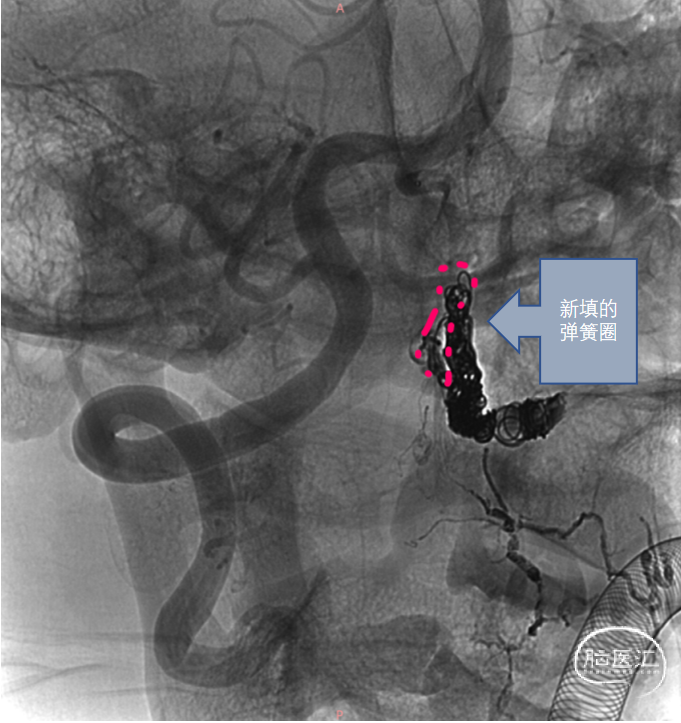

弹簧圈精准填塞瘘口

Onyx加固封堵瘘口

2、虽然不少文献认为显微手术是治疗CCJ AVF首选的治疗方式,但是对于解剖部位难以暴露,血管条件满足导管到达瘘口的CCJ AVF,血管内介入治疗仍是一种有效的治疗方案。介入治疗的目标是闭塞瘘口,保持正常供应神经的血管,缓解静脉高压。本例案例供血侧的椎动脉由于上次手术封堵,缺乏良好通路,因此采用了对侧椎动脉“翻山”技术,将微导管超选至瘘口处。考虑到该病例瘘口较大,流量大,我们直接将弹簧圈在瘘口处以及左侧椎动脉的PICA近心端成篮的方式,限制栓塞材料过度弥散,精准封堵瘘口。

2、介入治疗前需要明确CCJ-AVF的血流构筑学,瘘口的确切封堵对于介入治疗尤为关键。使用栓塞剂时,避免过度弥散,导致正常供血动脉及引流静脉回流受阻。可采用瘘口附近填塞弹簧圈等各种方法,限制栓塞剂的弥散,使其精准栓塞瘘口。

本病例的治疗难点集中于两点:其一,既往介入手术导致患侧椎动脉通路受阻,需另辟介入路径;其二,瘘口高血流量对栓塞材料稳定性提出极高要求。治疗团队应用对侧椎动脉“翻山”技术,成功建立逆向通路,突破解剖限制,展现了血管内介入操作的精准性与灵活性。针对瘘口高流量的挑战,术者采用弹簧圈于瘘口及左侧椎动脉PICA近心端“成篮式”填塞,这一策略巧妙平衡了瘘口完全闭塞与重要穿支血管保护的双重需求,体现了“精准栓塞”的核心治疗原则。